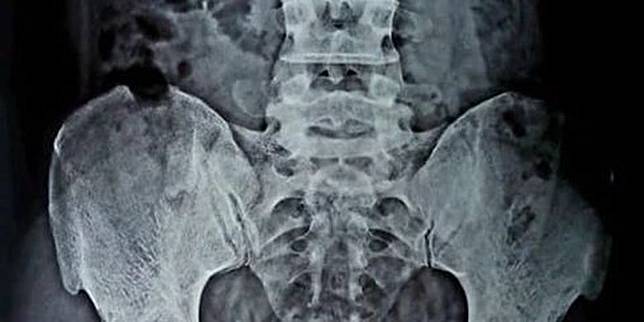

Saya telah melakukan operasi selama 25 tahun tetapi ini adalah pertama kalinya kasus seperti itu terjadi di meja operasi kata walliul seperti dilaporkan oleh hindustan times dikutip senin 8 6 2020. By zihan fajrin minggu 7 juni 2020 16 20 wib. Karena pasien berbohong tentang objek yang ditelannya dokter harus bekerja ekstra karena harus memeriksa sistem pencernaan terlebih dahulu. Hasil penglihatan tubuh pasien menggunakan sinar x ray yang merasakan nyeri akibat kabel charger menyangkut di kantung kemih.

Di sana terungkap adanya sebuah kabel charger pengisi daya ponsel berwarna hitam di kandung kemih pria tersebut. Dokter terkejut temukan kabel carger handphone di kandung kemih pria ini tim dokter di india berhasil mengangkat kabel cahrger yang memiliki panjang hampir dua kaki 50 cm dari kandung kemih pria berusia 30 tahun itu. Hal aneh terkait gadget terjadi di india dilaporkan seorang pria berusia 30 tahun mengeluhkan rasa sakit di bagian perut. Dokter temukan kabel charger di kandung kemih seseorang yang sakit perut di india seorang dokter mengoperasi seseorang yang pada kandung kemihnya terdapat kabel charger ini penyebabnya.